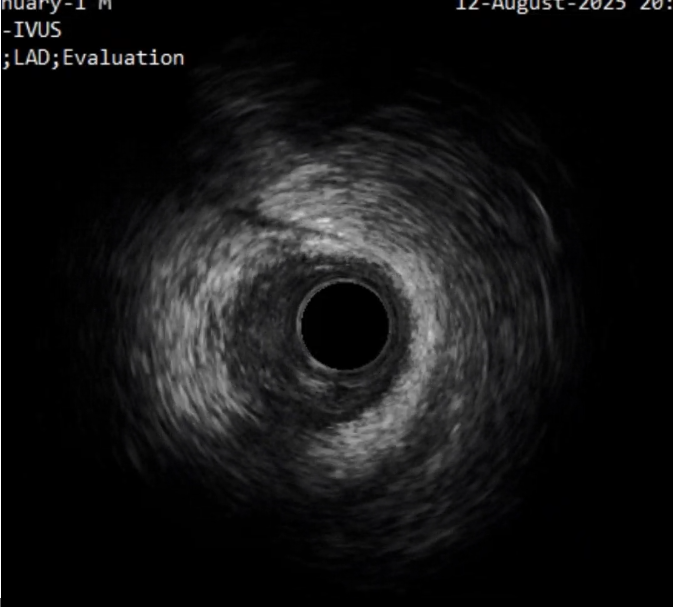

首先进行正向准备,对角支回撤IVUS明确CTO入口,Pilot200导丝进入

IVUS证实导丝进入CTO入口正确

远端导丝位于真腔内;中段可见夹层及血肿;CTO段部分位于假腔

(2)在实际操作过程中,冠脉CTA可以协助评估血管形态,导丝对吻、Knuckle技术、Carlino技术、导丝升级则可以帮助导丝前进,同时联合应用血管内超声检查可以明确管腔和导丝的位置关系。

③ 重视IVUS在CTO病变中的重要指导作用。